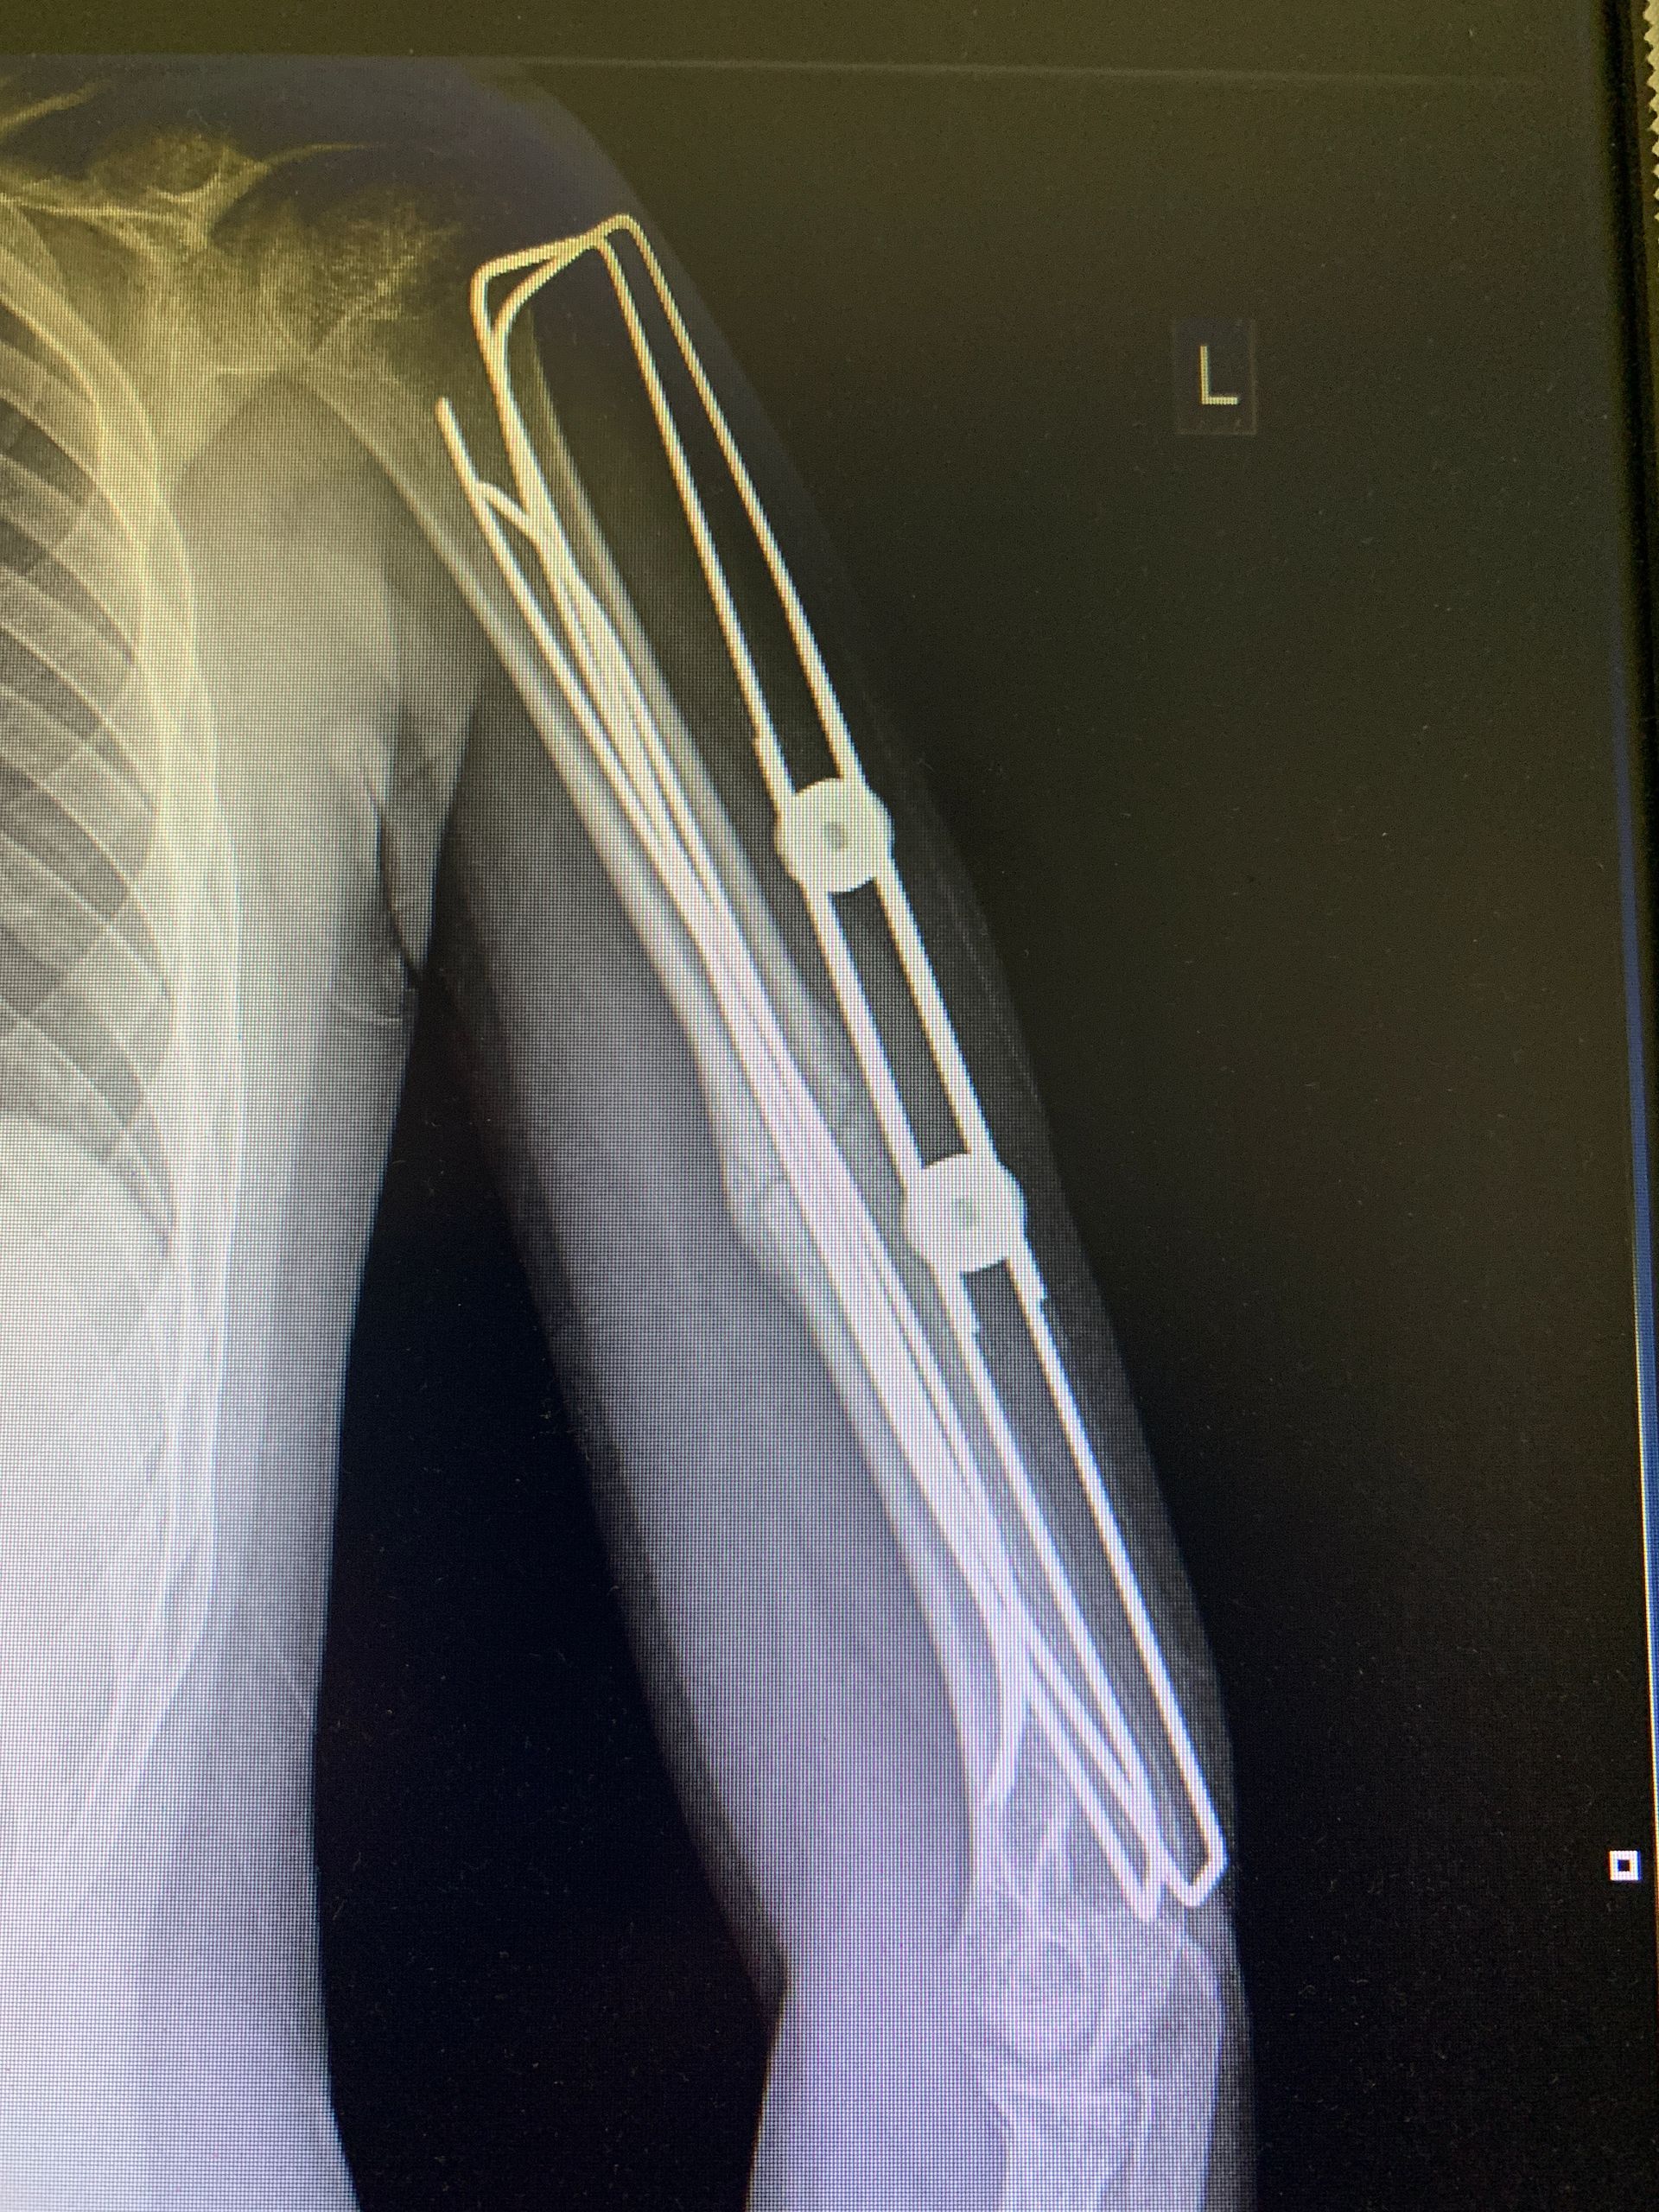

I NOSTRI INTERVENi

Dispositivi Technovare in sala

Radiografie di interventi realizzati con i nostri dispositivi in strutture pubbliche e private.